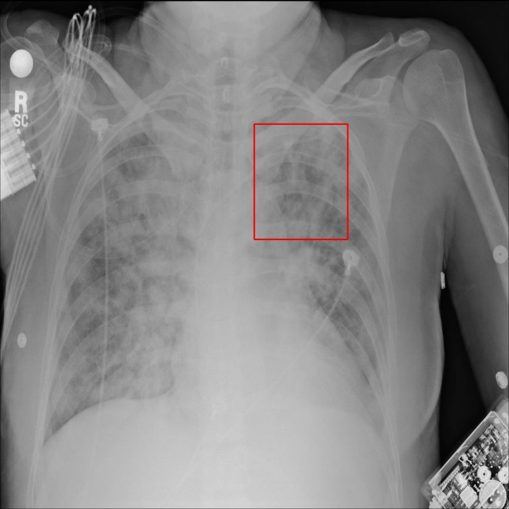

Figure 1: Examples of the five categories of X-ray images in the dataset, the first is a normal chest X-ray image without pneumonia, and the other four are images of four different types of pneumonia. The bounding boxes in the X-ray images are the area of the pneumonia lesions identified and marked by the doctor.

The dataset we employed consists of 20,012 X-ray images of pneumonia. As shown in Fig.1, there are five categories in the dataset, one category is normal X-ray images without pneumonia lesion, and the other four categories are X-ray images with different kinds of pneumonia. The pneumonia lesion areas of these four types of images are marked by highly-trained radiologists through bounding boxes, whose coordinates are available. We divided the pneumonia dataset into the training set and test set, and the rule of division is to randomly select 10% of images of each category to form the test set, and the remaining 90% is used as the training set. Each image is a single-channel chest X-ray with the resolution of 1024x1024. The dataset is available at https://god.yanxishe.com/23?from=god_home_list.